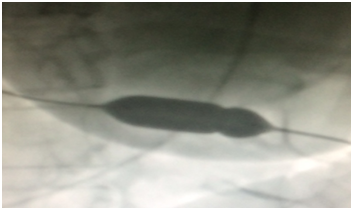

Bədxassəli şiş mənşəli perikardial effuziyalarda Perkutan Balon Perikardiotomiya və ya Plevroperikardial “pəncərə” Dərc edilib: Cild 11, Nömrə 1, 2017 / Nəşr tarixi: 31.05.2017

Firdovsi İbrahimov, Oqtay Musayev, Şəfa Şahbazova

Bədxassəli şiş mənşəli perikardial effuziyalarda Perkutan Balon Perikardiotomiya və ya Plevraperikardial “pəncərə” Dərc edilib: Cild 8, Nömrə 2, 2015 / Nəşr tarixi: 30.12.2015

Firdovsi İbrahimov, Şəfa Şahbazova